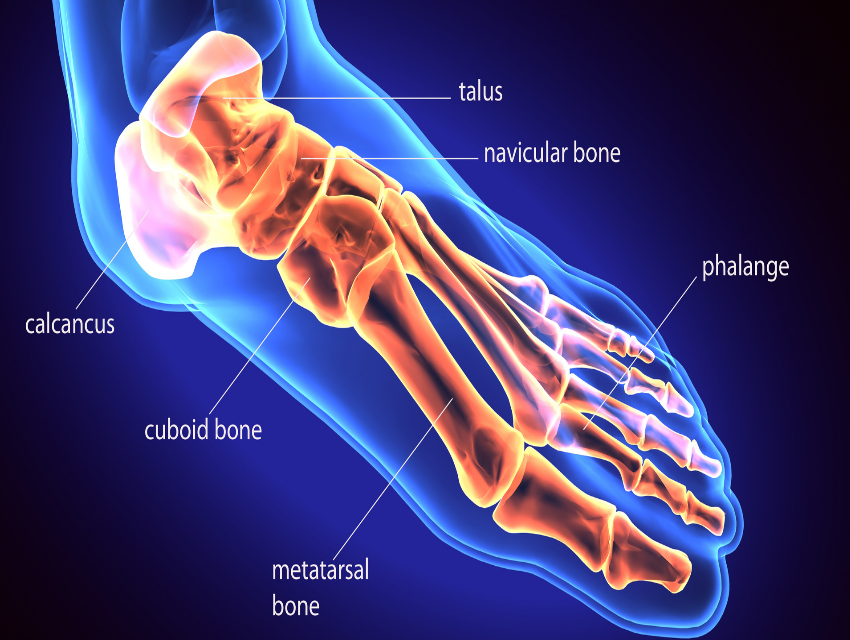

First the anatomy:

The foot contains multiple bones, connected by ligaments, capsules and muscles. Together they form arches, medially and at the front of the foot. A footprint shows a zone where there is no pressure.